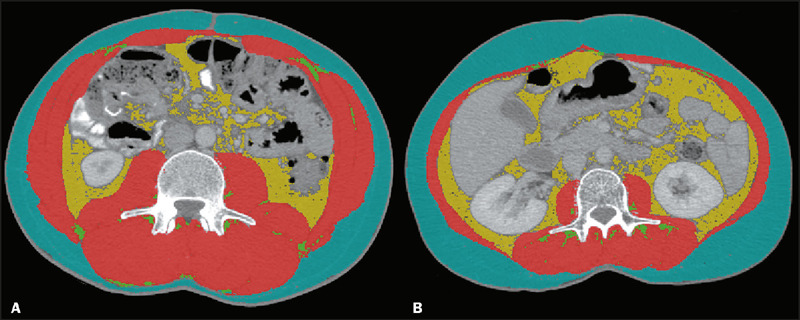

Objective: This study evaluates the effects of sarcopenia and cachexia on the quality of life (QoL) of patients with gastrointestinal cancer during their initial cycle of chemotherapy, emphasizing the significance of computed tomography (CT) in assessing muscle mass.

Materials and methods: In this prospective study, we evaluated 60 adult patients with gastrointestinal cancer who started chemotherapy between January and December of 2017. Sarcopenia was diagnosed on the basis of CT findings, and QoL was assessed with the European Organization for Research and Treatment of Cancer Quality of Life Questionnaire Core 30.

Conclusion: Among patients with gastrointestinal cancer submitted to chemotherapy, the chemotherapy-induced decline in QoL does not seem to differ significantly between those with cachexia or sarcopenia, as classified by CT-measured muscle mass, and those without. However, CT-based muscle mass evaluation remains crucial for guiding customized intervention strategies. Integrating this evaluation in radiological reports can provide valuable insights for planning specific care, thus improving patient QoL during treatment.